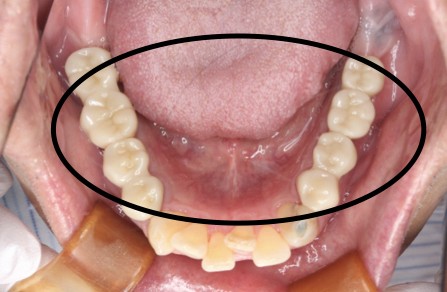

症例1

Before

After

主訴 | 奥歯で噛めるようになりたい |

|---|---|

治療内容 | 下顎の複数本の奥歯をインプラントにて再建 |

治療期間 | 6ヵ月 |

費用 | 200万円 |

副作用・リスク | ・術後に患部に腫れや痛み、違和感などが生じることがあります。 |